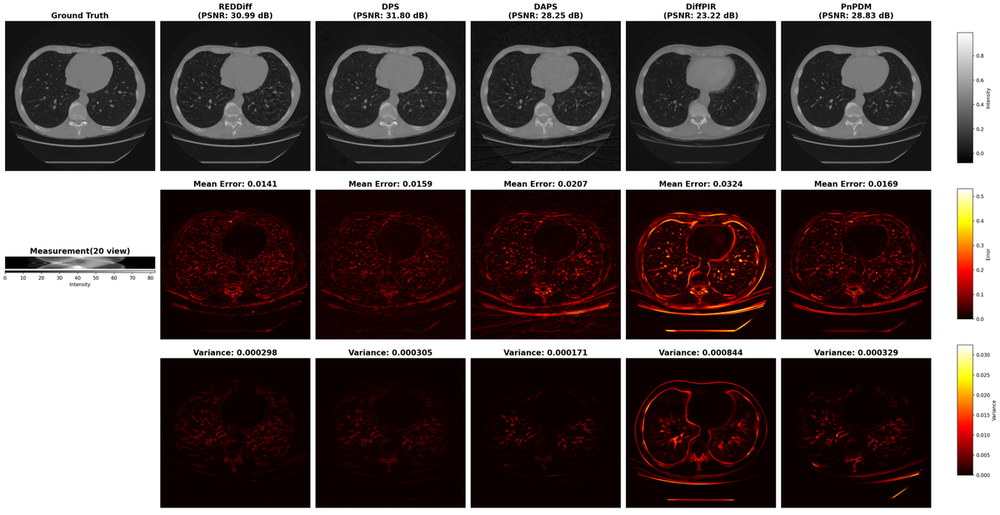

We summarize real-data results using three complementary views: (i) quantitative results with both accuracy and variance metrics across three tasks (Table 2); (ii) qualitative results with reconstructions, error maps and variance maps (e.g., Figs. 7 and  9 ), and (iii) an accuracy–uncertainty summary plot (Fig. 6). In the qualitative figures, the top row shows the highest-PSNR reconstruction among the K=100K=100 samples for each solver (PSNR reported); the middle row shows the corresponding error map with mean absolute error over pixels; and the bottom row reports the pixel-wise variance map aggregated over all KK samples, together with the spatially averaged variance reported.

Figure 7: Sparse-sampling MRI under ×4\times 4 acceleration rate (AR=4).

Figure 8: Out-of-distribution reconstruction result of 20-view CT using DAPS and REDDiff. The red bounding box shows the cancer region annotated by clinicians. The average PSNR of the entire image is 24.89424.894 dB and 25.30625.306 dB respectively while the average PSNR of the cancer region is 23.72823.728 dB and 23.21823.218 dB.

Several solvers that achieve similar PSNR and visual reconstruction quality, can exhibit substantially different uncertainty behaviors, both in the magnitude and the spatial structure of the estimated variance. For example, DAPS consistently produces a visible background variance across settings in Fig. 7 and 9, and also yields inflated variance along observed directions in Toy Experiment 2 (Fig. 4). Solvers also differ in the stability of their uncertainty behavior across tasks: the MAP solver REDDiff repeatedly shows near-zero variance, consistent with its point-estimation nature, whereas some heuristic solvers are less stable across settings. In particular, DPS shows relatively small variance in Toy Experiment 2 and the CT task, but much larger variance in linear inverse scattering and MRI. This variability is likely driven by sensitivity to algorithmic hyperparameters.

How does uncertainty behavior relate to accuracy performance?

In principle, reconstruction accuracy and uncertainty quantification are not necessarily related. For instance, REDDiff often achieves strong accuracy but produces near-zero variance, which is not a meaningful representation of uncertainty. Moreover, higher accuracy does not imply larger or smaller variance: in the 360-receiver inverse scattering (Fig. 9), DDNM and DDRM differ by roughly 55 dB in PSNR yet exhibit very similar variance levels. These results highlight that accuracy and uncertainty capture two independent aspects of PnPDP solvers, and both must be evaluated explicitly. These phenomenon are consistent with our toy simulation results (Fig. 5), where solvers with similar RMSE have largely different coverage, and some solvers achieve lower RMSE do not recover the observed and null direction variance well.

How does uncertainty behave in OOD recontruction?

Different solvers shows different behaviors on OOD compared with in-distribution reconstruction. As illustrated in Fig. 8, DAPS produces visually reasonable reconstruction but does not exhibit an increase in uncertainty at the tumor region for OOD test image, while other solvers exhibit an obvious increase in uncertainty on the OOD image(Fig. 10).